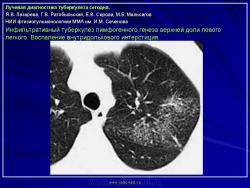

Лучевая диагностика туберкулеза сегодня

Я.В. Лазарева, Г.В. Ратобыльский, Е.В. Серова, М.Б. Мальсагов

НИИ фтизиопульмонологиии ММА им. И.М. Сеченова